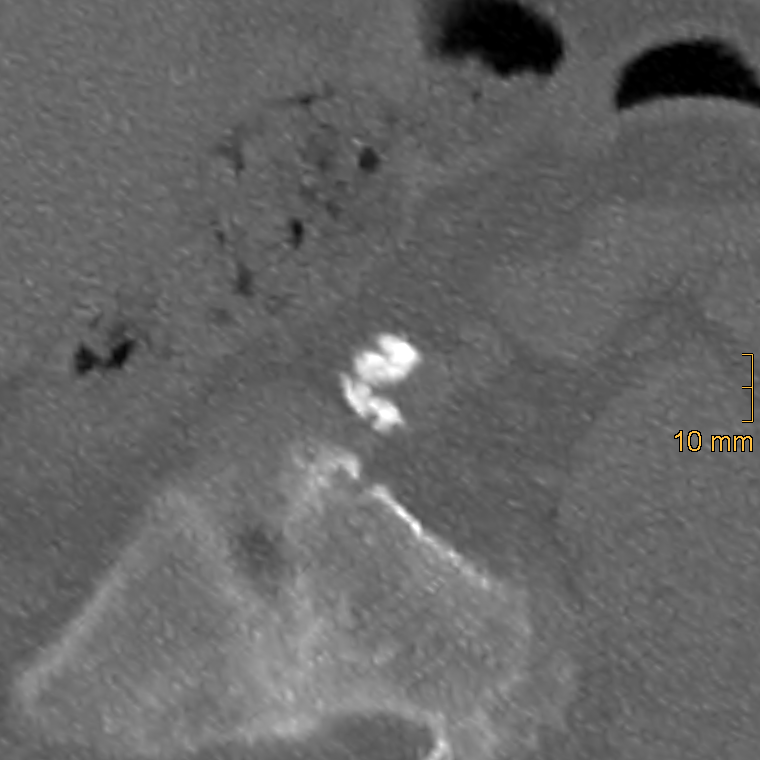

Iliac calcification was assessed using a semi-quantitative method described by Davis et al. [26]. Both common iliac arteries (CIA) and external iliac arteries (EIA) were evaluated bilaterally using standard bone window settings (window width = 2500 HU; window level = 300 HU). The CIA was defined from the aortic bifurcation to the iliac bifurcation, and the EIA from the iliac bifurcation to the level of the superior aspect of the femoral head. Each vessel segment was scored in three domains: morphology (0–3), circumference (0–4), and length of involvement (0–4). To ensure accurate assessment, multiplanar reformations were generated to correct for vessel tortuosity and to obtain orthogonal cross-sectional views, which is essential for the evaluation of calcification morphology and circumferential extent, whereas the longitudinal extent of calcification was assessed on standard axial images. Morphology was graded as follows: 0 = no calcifications, 1 = thin linear (≤1 mm), 2 = thick linear (>1 mm), 3 = bulky (>2 mm, convex luminal margins). Representative examples of morphologic grading are shown in Figure 2, Figure 3 and Figure 4. Circumference and length of involvement were scored as 0 = no calcifications, 1 = 1–25%, 2 = 26–50%, 3 = 51–75%, 4 = 76–100%. The highest score per segment was used in cases of multiple calcified regions. For each patient, bilateral scores were summed and averaged, resulting in the common iliac artery calcification score (CIACS) and the external iliac artery calcification score (EIACS). Both scores were subsequently combined to generate the total iliac artery calcification score (TIACS). Severity was classified as follows: 0–3.75 = none to mild, 4–7.75 = moderate, 8–11 = severe.

Figure 4.

Example of a thick, bulky calcification with convex luminar margins in the left common iliac artery, corresponding to a morphology score of 3.